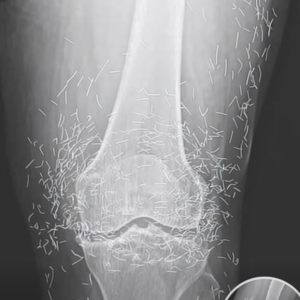

Doctors Stunned by Gold Needles Found in Woman’s Knees During Routine X-Ray

When a 65-year-old woman in South Korea visited the hospital for what she thought was routine knee pain, she expected a familiar diagnosis — arthritis. Instead, her X-ray revealed…